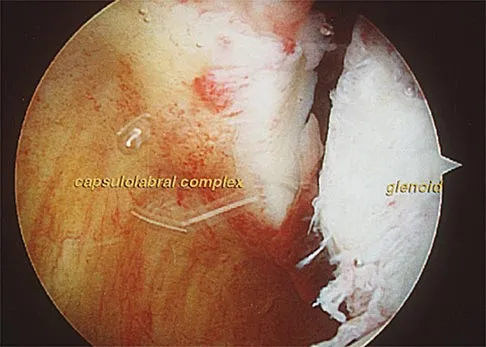

An 18-year-old hockey player sustains an acute anterior shoulder dislocation that requires manual reduction. At arthroscopy, the lesion shown in Figure 24 will be observed in what percent of patients?

Explanation